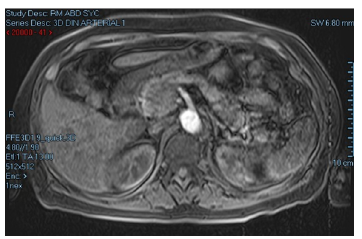

An abdominal magnetic resonance imaging (MRI) was performed on the second day of her stay on the general floor, revealing a mass of 33x30mm between the head and the uncinate process of the pancreas, with no evidence of metastasis (Figure 1). Due to the high suspicion of a neuroendocrine tumor, 6 days after admission a chromogranin A (CgA) measurement was requested, obtaining a value of 477 ug/L (0-100), as well as a 5-HIAA urine test, the result of which was not reported.

Abdominal MRI showing mass between the head and the uncinate process of the pancreas.

Figure 1: Abdominal MRI showing mass between the head and the uncinate process of the pancreas.

Source: Document obtained during the course of the study.